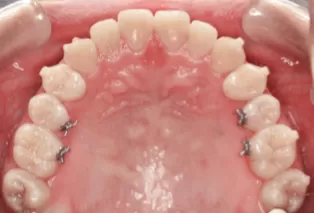

Intraoral photos